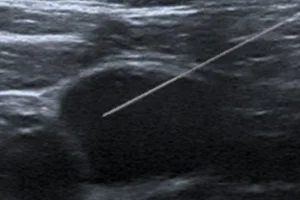

Lorsqu’une lésion suspecte (ACR4 et ACR5) est visible en échographie, on réalise une microbiopsie sous guidage échographique, à l’aide d’un pistolet biopsique automatique.